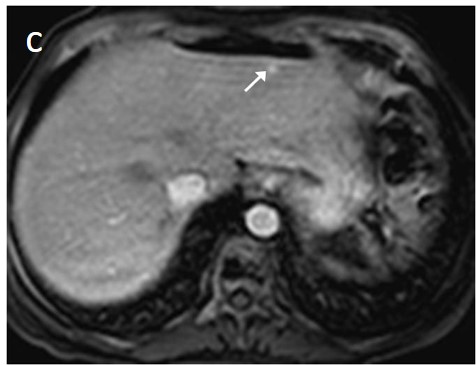

The presence of a capsule (Figure 12) is a major finding according to LI-RADS, but not EASL. The capsule is a characteristic feature of progressed HCC and is absent in dysplastic nodules or early HCCs. It shows low T1 and T2 signal intensity and enhancements on the portal and delayed phase at 3 min after contrast injection (or transitional phase if hepatospecific contrast agent is used); on the contrary, corona enhancement occurs earlier on the arterial phase. A capsule should be thicker than the fibrous septa of cirrhosis, which also show delayed enhancement. An intact capsule on imaging has been associated with lower recurrence rates after treatment [137], while extracapsular tumor extension predicts poor survival [138]. It should be stressed, however, that an encapsulated progressed HCC has a worse prognosis than an unencapsulated early HCC; the presence of a capsule confers a better prognosis only when the encapsulated tumor is compared to HCCs of a similar size and grade with breached capsules or without a capsule.

Figure 12. A large HCC is depicted in the right liver lobe of this 81-year-old man. The tumor is surrounded by a capsule, nicely seen as a thin, low signal line on the fat-suppressed T2 sequence (arrowheads) (a) and shows inhomogeneous but predominantly high T2 signal intensity. Areas of fat are clearly shown in the in/out of phase images (asterisk) (b,c). This marked heterogeneity is known as the “mosaic” pattern. After contrast administration, mottled arterial enhancement is noted (d); definite wash-out and capsular enhancement (arrows) are seen on the portal phase (e).

Fatty change is encountered in approximately 40% of early HCCs [143]. With increasing tumor size and histologic grade, fat usually regresses and the percentage drops to 6% in moderately-differentiated HCCs [144], only to increase again in highly de-differentiated tumors. This occurs along with the diminished arterial supply, suggesting a connection between reduced blood flow, hypoxia, and steatogenesis [145]. MRI is superior to CT in detecting fatty change with the use of chemical shift sequences, which show the characteristic signal drop on the opposed-phase compared to the in-phase (Figures 12 and 13). Intratumoral fat can also be used to exclude cholangiocarcinoma, which is also associated with cirrhosis. Nevertheless, the added value of fat identification in a HCC is debatable because, when detected, other more suggestive features (like the vascular pattern) are already present [123].